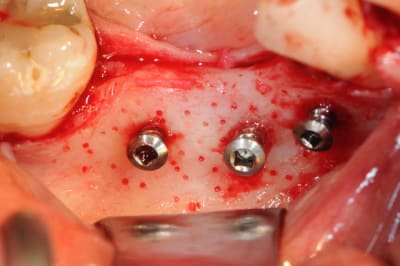

CAS 1

demande de restauration avec implant, mais, ne veut pas entendre parler de greffes et greffons.

la ROG lui semble plus "naturel".

1-2-3 situation de départ

4 après ouverture

7-8: et voilà 3 vis qui vont maintenir ma membrane au dessus de l'os.